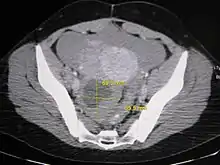

Further work up involves imaging, such as a pelvic ultrasound or CT scan.[7] Theca lutein cysts with diameters over 6 cm in size can be seen through these imaging modalities.[18] Benign ovarian cysts and complex cysts that are potentially malignant are distinguishable via ultrasounds.[19] Labs are also collected to evaluate leukocytes and tumor markers, such as beta-hCG and cancer antigen 125 (CA125).[20]

During pregnancy, ultrasonography is the first-line method for evaluating ovarian cysts. Both transabdominal and transvaginal route of ultrasonography are used with either two-dimensional or three-dimensional modalities.[3] Two-dimensional is more common, but three-dimensional can offer more results.[3] Doppler ultrasonography can also be used and is helpful at analyzing the characteristics of the cyst.[3] It can identify the presence of color flow within a septum as well as the presence of a solid component of the mass.[3] Ultrasonography is an effective tool for observing the progression or regression of the cyst.[3] Magnetic resonance imaging (MRI) is the second-line method used when ultrasonography cannot detect the cyst.[3] Cysts that are too large to be accurately analyzed by ultrasonography are typically when MRI would be used.[3] The advantages of MRI are its larger field of view and multiplanar capabilities.[21] In addition, pathologies such as infarctions and placental invasive disorders can be seen more clearly.[3] MRI is especially beneficial in gestational age and obese people.[3] MRI is also beneficial at preventing the exposure of ionizing radiation to the fetus during pregnancy.[22] Both ultrasonography and MRI show enlarged ovaries with multiple theca lutein cysts.[3]